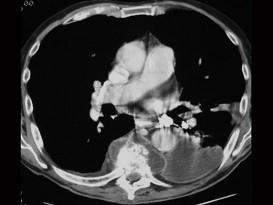

问题 男,71岁,背部酸痛,低热,乏力,消瘦2个月余,请结合影像学检查选出最可能的诊断 ( )

选项 A、椎体压缩骨折 B、阻滞椎 C、化脓性脊柱炎 D、脊椎结核 E、脊柱转移瘤

答案 D